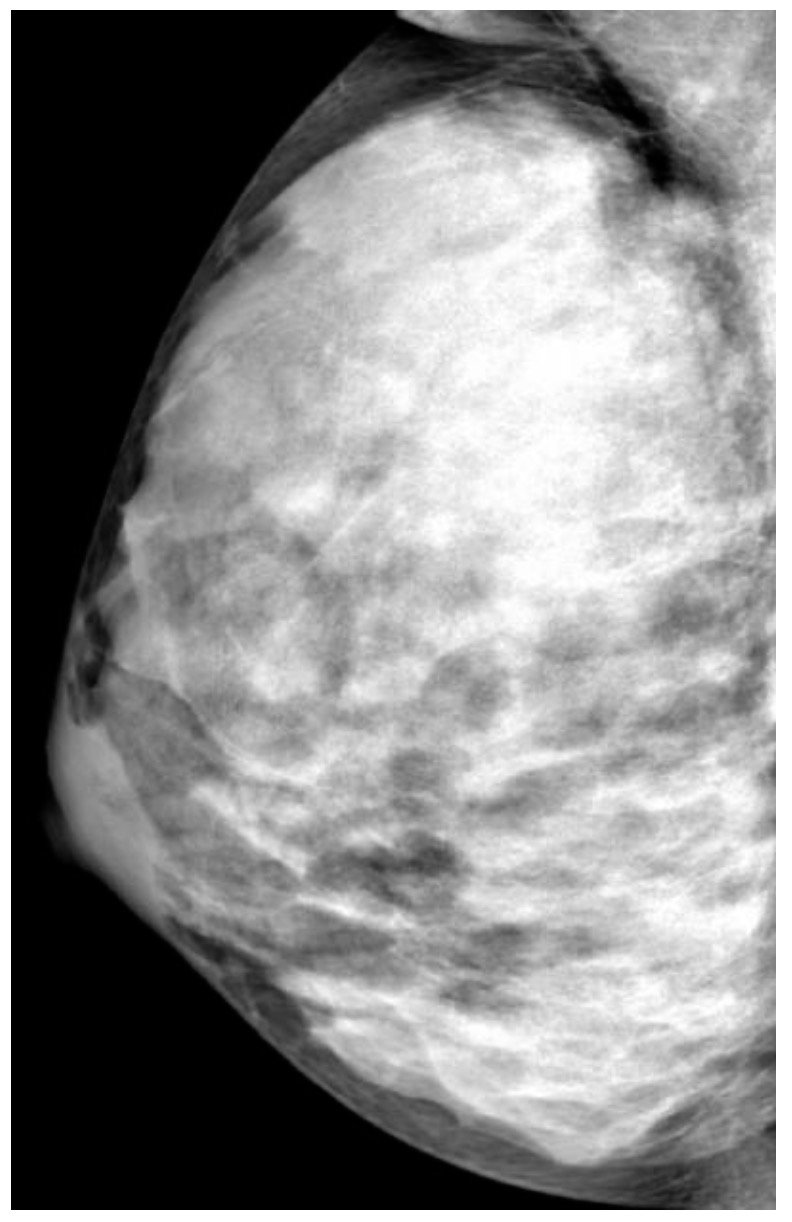

Extremely Dense Breast Tissue (IMAGE)

image approved use from RADIOLOGICAL SOCIETY OF NORTH AMERICA

Virtually all women of childbearing-age have very dense breasts by design because what is called “dense tissue” is simply “everything but the fat” and we’ve known since at least 2015 that “dense breast tissue absorbs significantly more radiation during mammography compared to fatty tissue,” per the OBGYN’s 2015 Committee Opinion which won’t last much longer on the internet with the censorship the medical mafia feels is necessary but I have downloaded the pdf at that link which is easier to read than their awful mishmash of this opinion (by design?) so look for the pdf link on the right side.